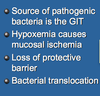

Review Card: Pathophysiology of Gastric Dilatation Volvulus

Respiratory System: Increased CO2, Respiratory Acidosis

Cardiac System- Decreased Preload and Afterload, Arrhythmias

Gastric System- Mucosal Sloughing, Bacterial Translocation